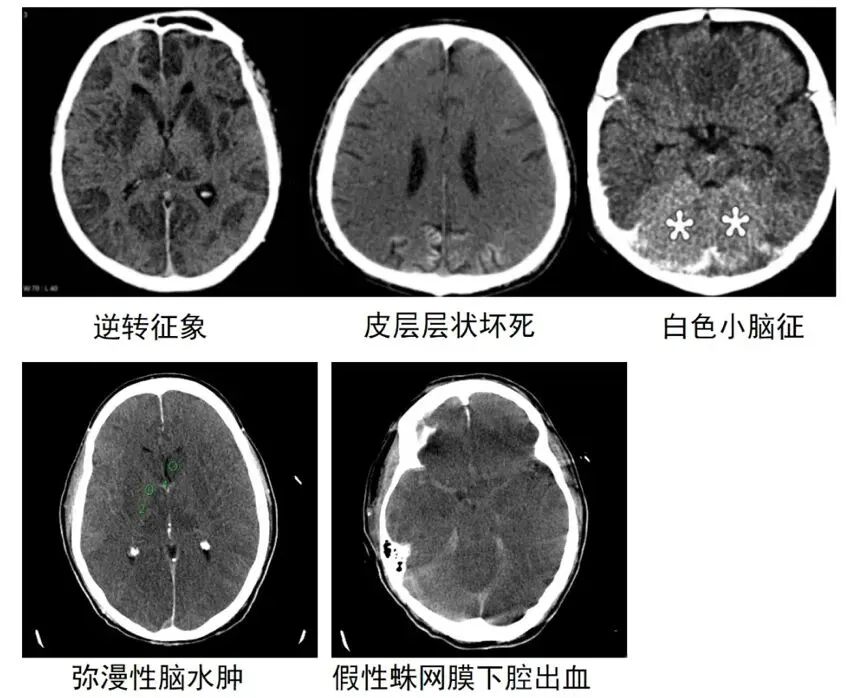

弥漫性脑水肿

脑室变小,脑沟脑裂变窄,脑灰白质分男不清或消失。

逆转征象

正常灰白质的CT值逆转,少数患者在24小时内可见。这一征象是由于弥漫性脑水肿引起颅内压增高,从而深部髓质静脉部分流出受阻扩张所致。

白色小脑征

有研究认为这属于逆转征象的一部分,由于大脑半球存在弥漫性水肿密度减低,导致小脑和脑干呈相对高密度,这一征象的出现表明脑损伤严重且预后不良。

皮层层状坏死

灰质结构上分6层,其中第3层最易受缺血缺氧损害,表现为皮质的线样高密度影,是在大脑氧气和葡萄糖的供应不足的情况下,选择性神经元坏死以满足区域需求。

假性蛛网膜下腔出血

脑水肿和颅内压增高导致脑实质密度减低,而静脉结构充血扩张,从而出现蛛网膜下腔似出血的高密度影。在20%心肺骤停后的患者中可发生,通常在复苏后3天内,表明严重的脑损伤提示预后不良。